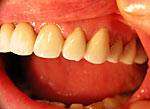

Frontzahn-Implantation: